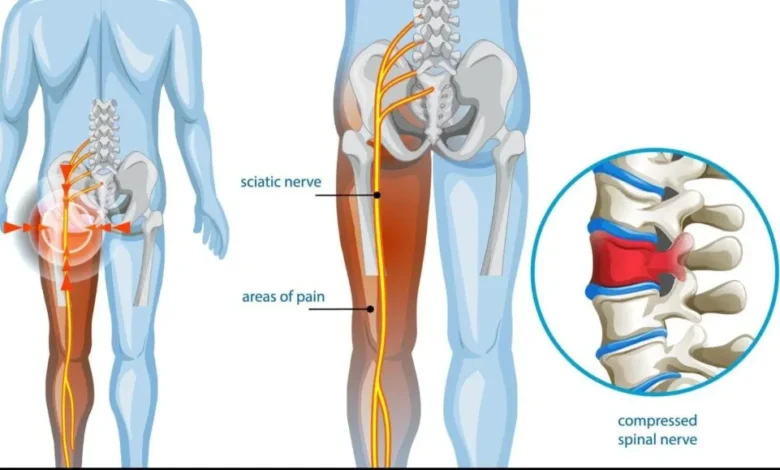

درمان سیاتیک بدون نیاز به دارو و مداخلات تهاجمی، یکی از موضوعات مهم در حوزه سلامت است که اخیراً متخصصان ابعاد تازهای از آن را روشن کردهاند. درد سیاتیک که معمولاً به صورت یک درد تیرکشنده از کمر به سمت باسن و پاها احساس میشود، میتواند فعالیتهای روزمره را به شدت مختل کند.

بر اساس گزارشهای جدید، بسیاری از افرادی که با این مشکل دستوپنجه نرم میکنند، میتوانند با استفاده از روشهای غیردارویی و تغییر در سبک زندگی، در عرض چند هفته بهبود یابند. این رویکردها بر تقویت عضلات مرکزی، افزایش انعطافپذیری و کاهش فشار از روی عصب سیاتیک تمرکز دارند.